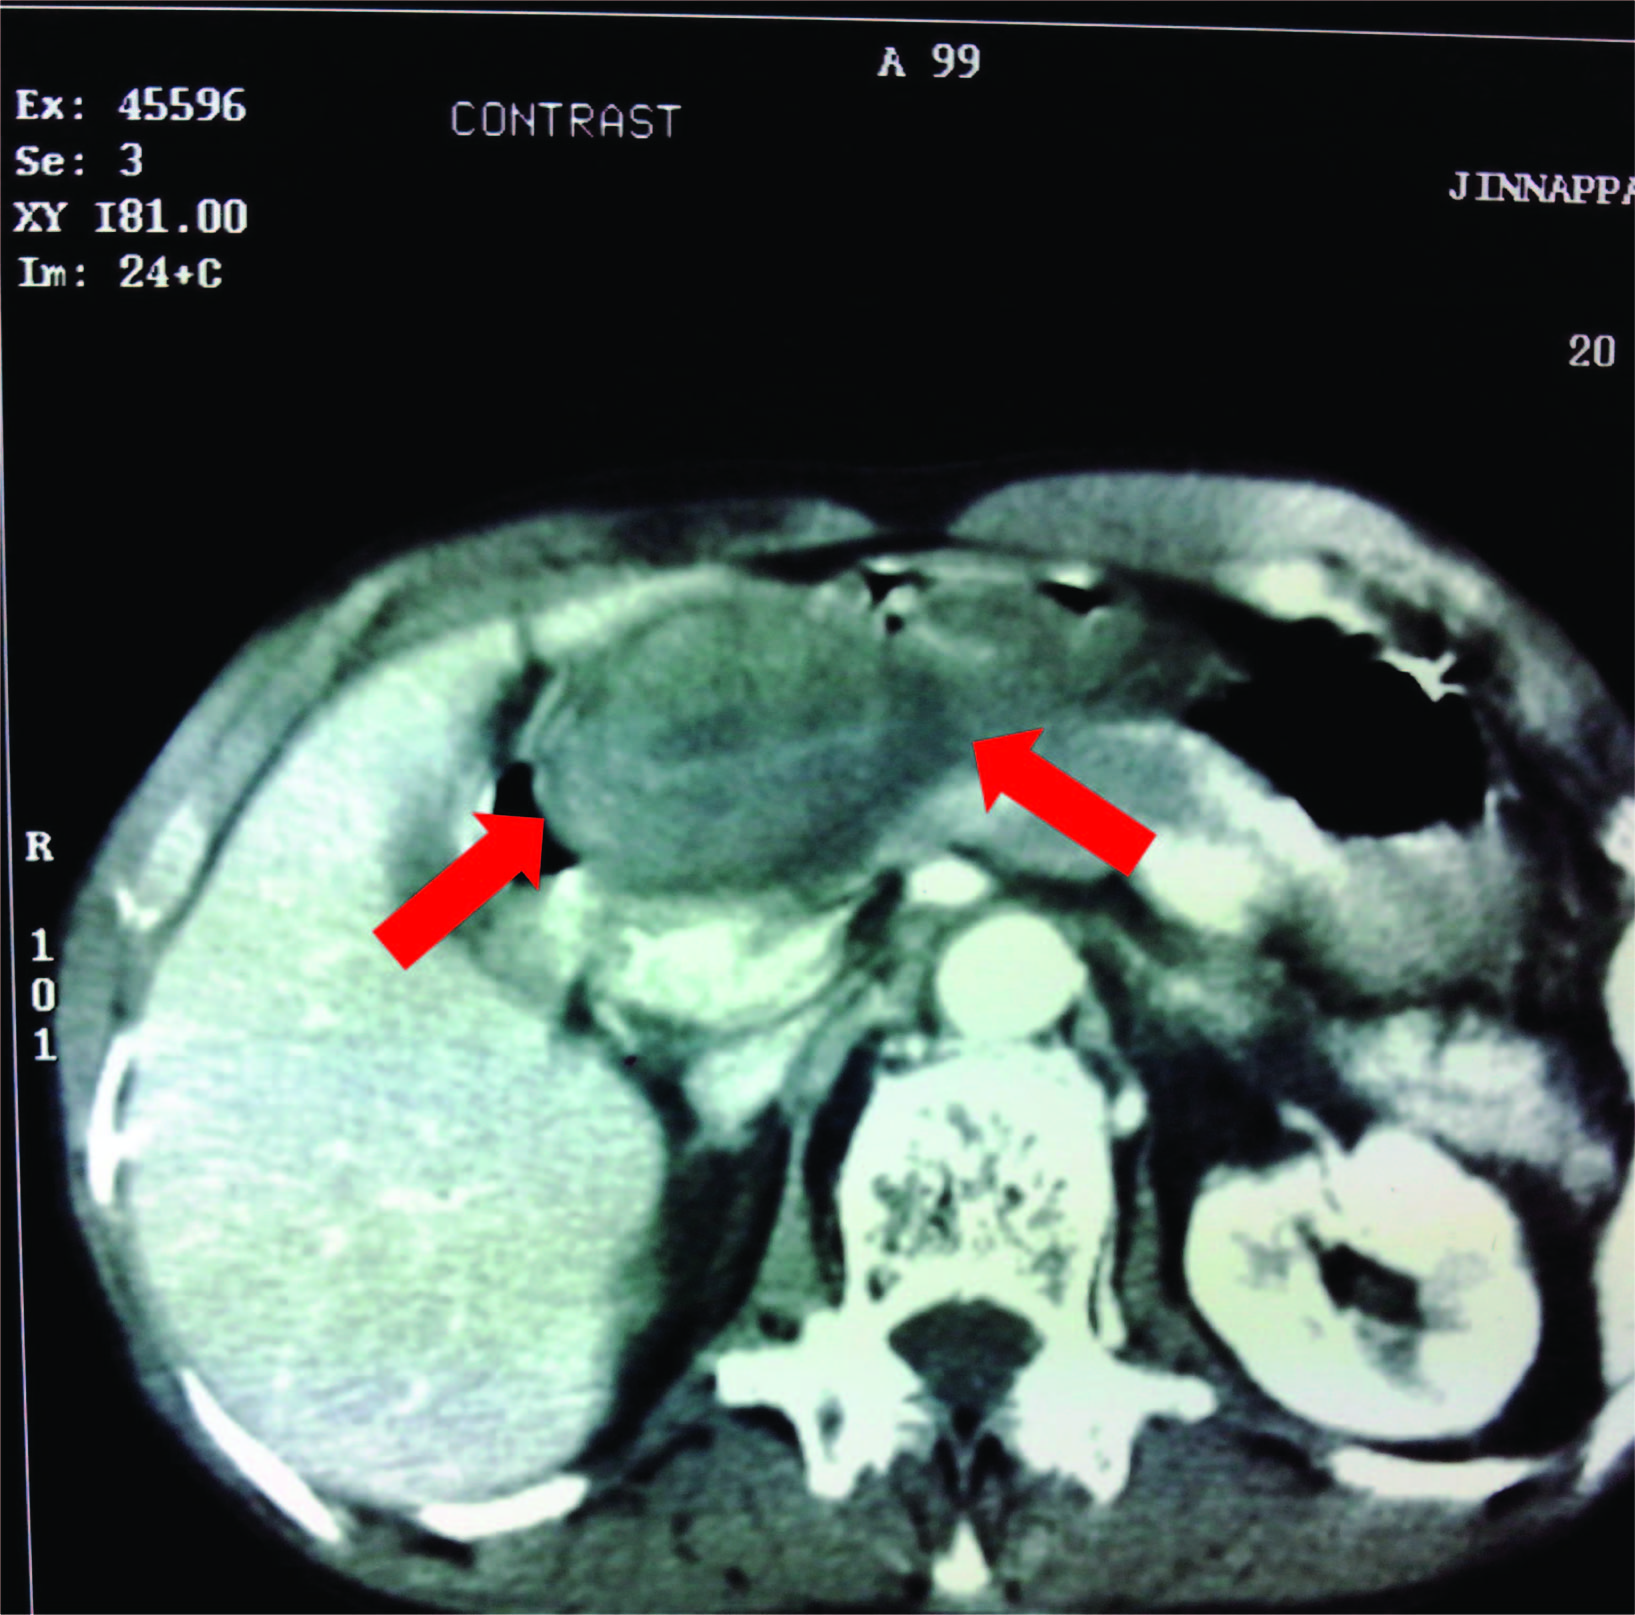

CECT (Contrast Enhanced Computerised Tomography) abdomen revealed a polypoidal lesion at pyloro-duodenal junction growing concentrically along the pylorus, occluding the lumen [Table/Fig-1]. It extended eccentrically along first part of duodenum with anchoring of the mass to pyloro- duodenal junction causing partial organo-axial volvulus which is a possibility of GIST.

CECT showing polypoidal lesion in pyloroduodenal junction narrowing the lumen with intraluminal infiltration